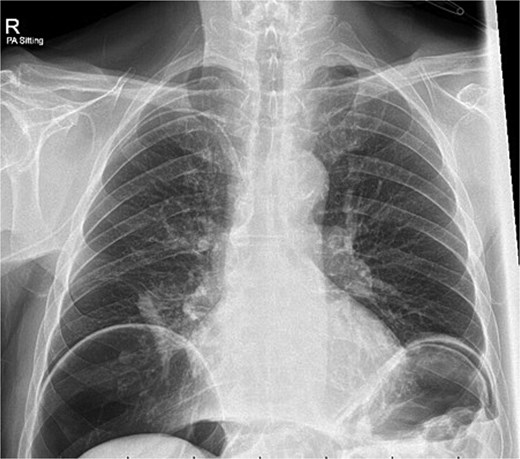

A chest x-ray confirmed new right lower lobe consolidation and demonstrated interval development of massive pneumoperitoneum compared to the CT scan 3 days prior (Fig. 2). A repeat CT scan was therefore undertaken, revealing large volume pneumoperitoneum with free gas locules but no rectal contrast extravasation at the region of the anastomosis (Fig. 3).

Over the following 2 weeks, the patient’s vital signs remained in normal range and abdomen was benign on serial examination. Clinical improvement was evidenced by the reduction in nasogastric output and return of bowel movements. Enteral feeding was established and TPN ceased. IV antibiotics were also stopped following a 7 day course. Repeat chest X-ray at day seventeen of admission demonstrated a reduction in volume of pneumoperitoneum. He was successfully discharged home 24 days following the initial sigmoid colectomy.